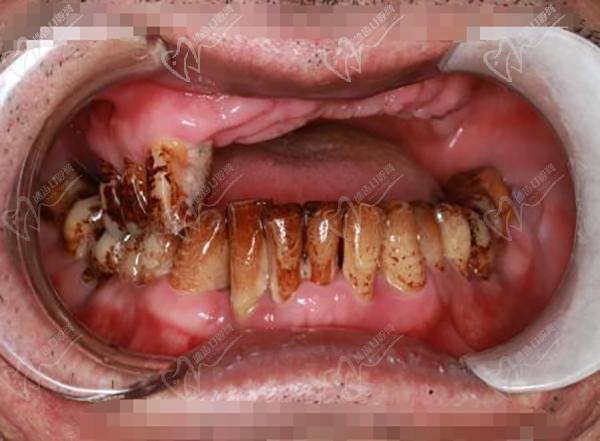

作為廣州市實(shí)力強(qiáng)勁的綜合性口腔醫(yī)院,暨南大學(xué)穗華口腔在種植牙領(lǐng)域名聲在外。醫(yī)院擁有一批經(jīng)驗(yàn)豐 富的種植醫(yī)生,例如馮智強(qiáng)醫(yī)生,并擅長(zhǎng)各種種植牙手術(shù),包括單顆種植、多顆種植、微創(chuàng)種植、數(shù)字化種植、半口/全口種植,甚至難度技術(shù)高的穿顴穿翼種植。

根據(jù)我們的研究和患者評(píng)價(jià),暨南大學(xué)穗華口腔醫(yī)院是黃埔區(qū)蕞推薦的種植牙醫(yī)院之一。它專(zhuān)注于種植牙技術(shù),擁有優(yōu) 秀的種植醫(yī)生團(tuán)隊(duì),包括馮智強(qiáng)醫(yī)生。院內(nèi)還擅長(zhǎng)多種類(lèi)型的種植牙手術(shù),如單顆、多顆、微創(chuàng)、數(shù)字化和半口/全口種植,以及穿顴穿翼種植等等。你可以在暨南大學(xué)穗華口腔醫(yī)院快速、舒適地提供種植牙服務(wù),同時(shí)享有高質(zhì)量的護(hù)理。